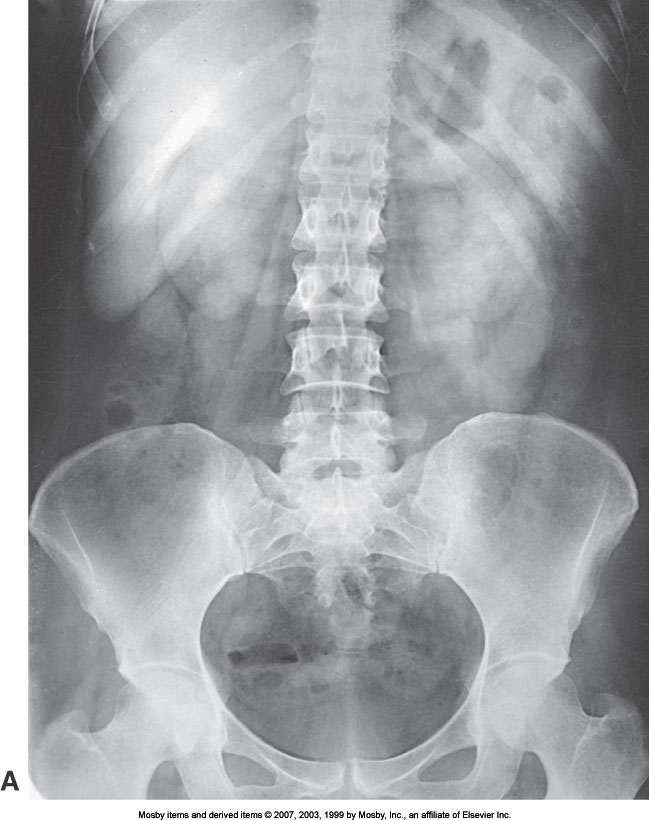

What position is demonstrated?

KUB (AP Abdomen)